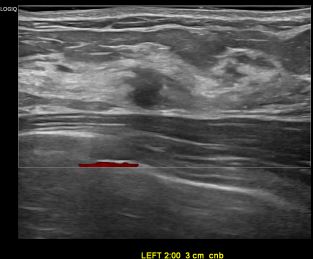

상기환자는 외부검진이상소견으로  내원하신40대중반

여성분으로 의심스러운 좌측혹 조직검사 시행해 침윤성암 으로 진단되었습니다